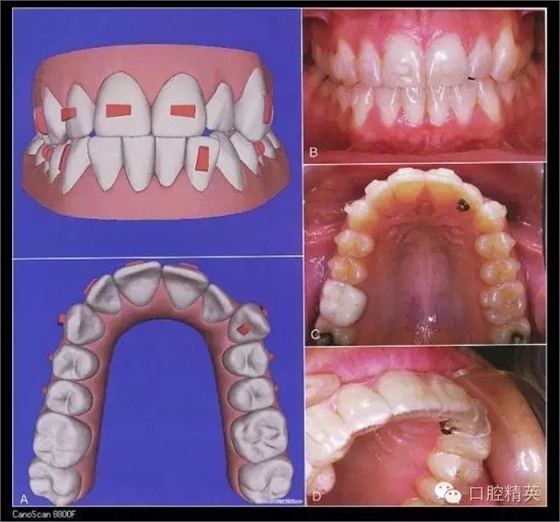

五、隱形矯治器

Invisalign隱形矯治器的原理是先在計算機里對醫(yī)生的印模進行三維建模,按照正畸醫(yī)生的指導(dǎo)來設(shè)計挪動牙齒,得到醫(yī)生的確認(rèn)后投入加工。每付矯治器少量移動牙齒,兩周更換一副矯治器,在1-2年后完成牙齒的矯治。因為材質(zhì)沒有金屬,受到很多白領(lǐng)的追捧,不過目前還不能夠治療所有的復(fù)雜病例。對付輕中度擁擠,輕度開合,牙縫散開等是不錯的選擇。